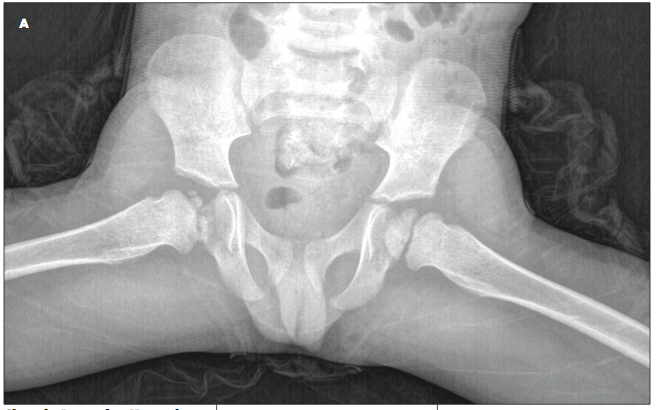

A 2 1/2-year-old boy was brought to the emergency department because of fever, cough, lower abdominal pain, and dysuria.